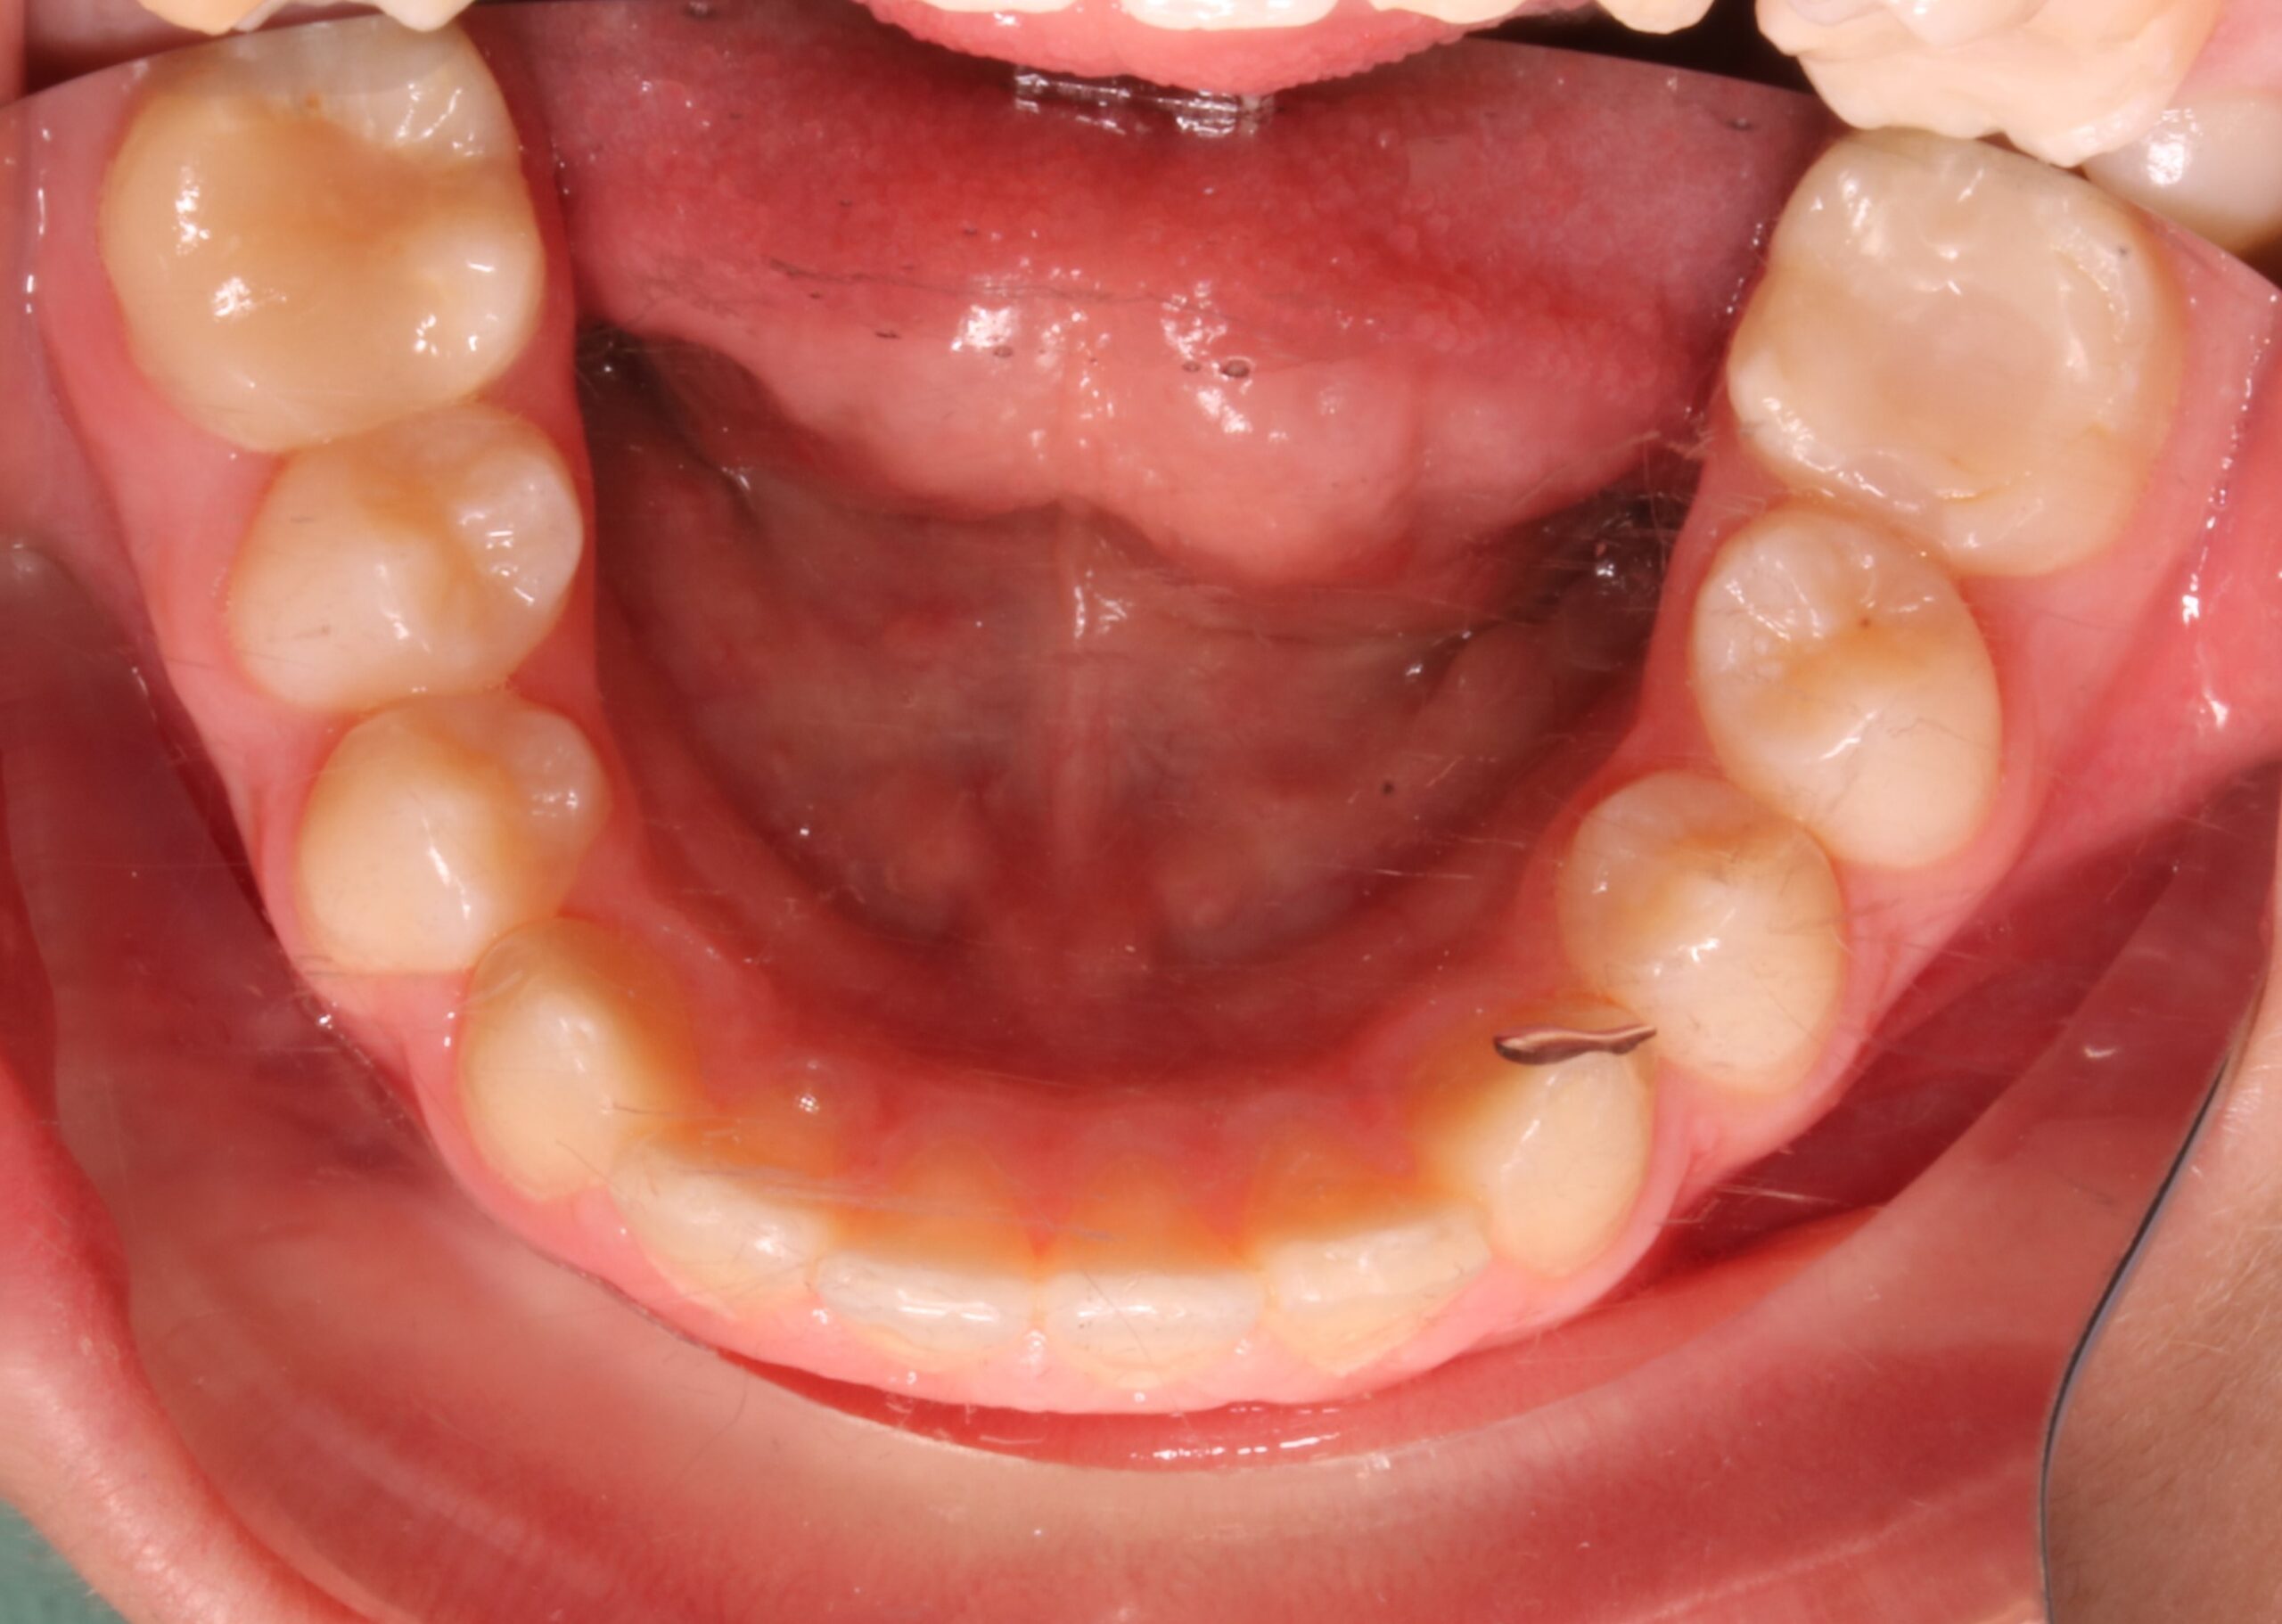

Nos encontramos con un caso en un timming adecuado para realizar un avance mandibular. También, nos favorece la inclinación el ángulo goniaco de 123 grados y la motivación del paciente. En contra nos perjudica la inclinación del incisivo inferior de 100 grados (lo podríamos controlar con microimplantes en la meseta inferior o alineadores, pero el paciente rechaza ambas opciones). Por otra parte,  en la radiografía frontal observamos un resto radicular en el 16, que decidimos extraer, y a petición del paciente, cerrar el espacio con mesialización del 17.

CLASE II MOLAR Y CANINA BILATERAL CON PERFIL DE MANDÍBULA RETRUSIVA AVANCE MANDIBULAR (CAMBIOS A NIVEL FACIAL+ CLASE I MOLAR Y CANINA)

RESTO RADICULAR DE 16 EXTRACIÓN DEL 16 Y MESIALIZACIÓN DE 17

FOTOGRAFÍAS DE INTERÉS